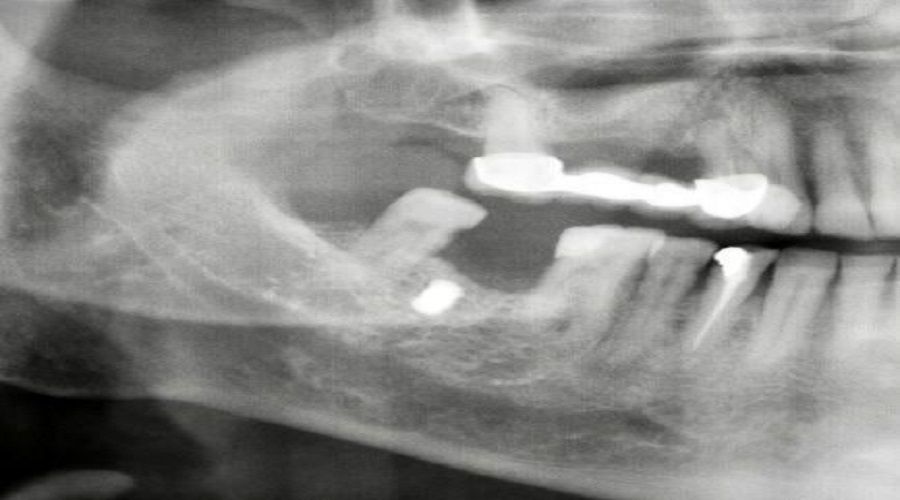

Diş tedavisi için hastaneye gelen Faik Akın'ı muayene eden Ağız ve Çene Cerrahı Dr. Öğretim Üyesi Yakup Gülnahar, hastanın röntgen filmine bakınca damağında bir nesne olduğunu belirledi. Hastanın ameliyatını gerçekleştiren Dr. Yakup Gülnahar, 1 saatlik operasyonla damağa saplanan demiri çıkardı.

Ameliyatı gerçekleştiren Dr. Yakup Gülnahar, "Hastanın muayenesinde rutin röntgen filmi istedik. Röntgenlerde hastanın yanağında bir cisim olduğunu anladım. Kendisine daha önce implant yaptırıp yaptırmadığını sordum. Kendisi implant yaptırmadığını söyledi. Bu sefer hastanın yanağında ne olabilir diye düşünürken hastanın 15 yıl önce benzinli odun testeresi ile çalışırken testerenin zincirinin koptuğunu ve etrafa saçılan parçalardan yanağına isabet ettiğini öğrendik. Hastamızı ameliyata aldık ve yanağındaki demir parçayı çıkardık. Hastamız da şu an gayet iyi bir durumda" şeklinde konuştu.